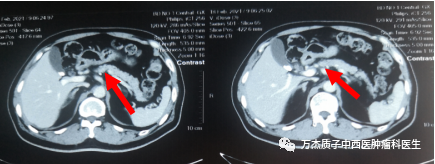

下图为质子治疗前肿瘤病灶显示情况,箭头所指处为胰腺肿瘤病灶

下图为质子治疗后半年复查的影像,显示肿瘤病灶缩小明显